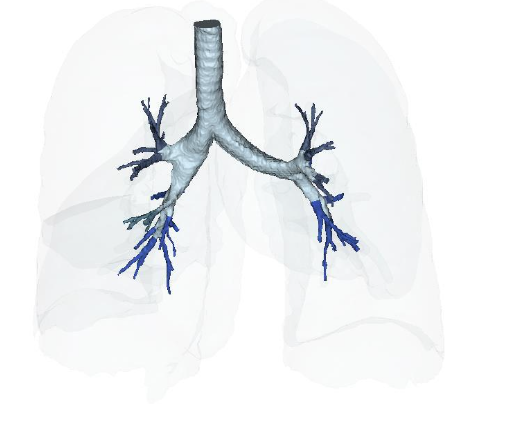

Figure 15A: Vascular Perfusion of Lungs Post-treatment IV deployment at 6 months. Figure 15B: Post IV deployment cSVF therapy in Long COVID-19 clinical trial NCT04326036 at 6 months. NOTE: Improved perfusion, throughout, but particularly in the lower distal lung. Figure 16: Restoration of the near terminal Tracheobronchial tree, pre-treatment showing blunting and loss of distal bronchiolar tree. Figure 16B: Post-treatment IV cSVF with elongation of distal bronchiolar tree at six months. NOTE: With this post-treatment changes with cSVF was an accompanying reduction in airway resistance and pressures within the lung parenchyma. Higher pressures in pre-treatment image were located in the Upper lobes (less efficient and higher pressures in pre-treatment), whereas the shift from upper to lower lung parenchyma accompanied Improve vascular supply and perfusion, and patients no longer experienced difficulties in inhalation capabilities.